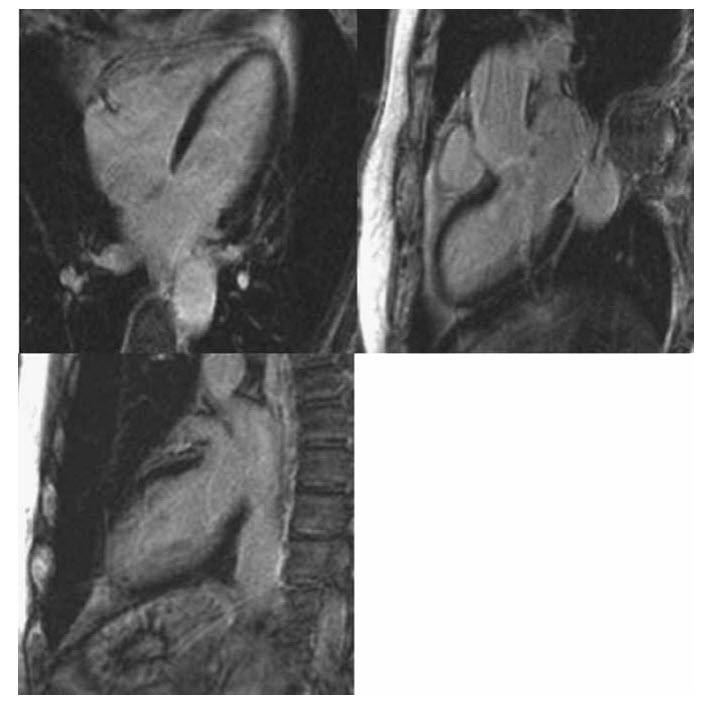

The late myocardial enhancement images are shown below

What is the diagnosis?

A. STEMI

B. Takotsubo

C. NSTEMI

D. Myocarditis

E. Hypertrophic cardiomyopathy